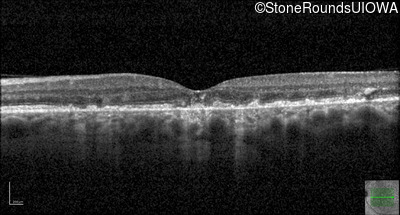

Age at visit: 49 years

This 49 year old man was first told he had a fundus abnormality on a routine eye exam at age 34. Ten years later he noticed some distortion just superior to fixation.

Pattern Dystrophy PRPH2 Gln239Stop CAG>TAG   AD